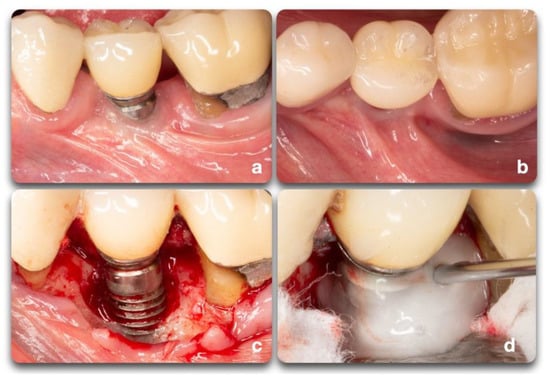

Figure 7.

Clinical scenario representing a peri-implant defect affecting implant #20. A lack of keratinized mucosa (a) and frenum pull (b) could have played an important role in the defect shown (c). After mechanical debridement with curettes and titanium rotary brushes, the surface was treated with 24% EDTA gel to provide the chemical surface decontamination (d).